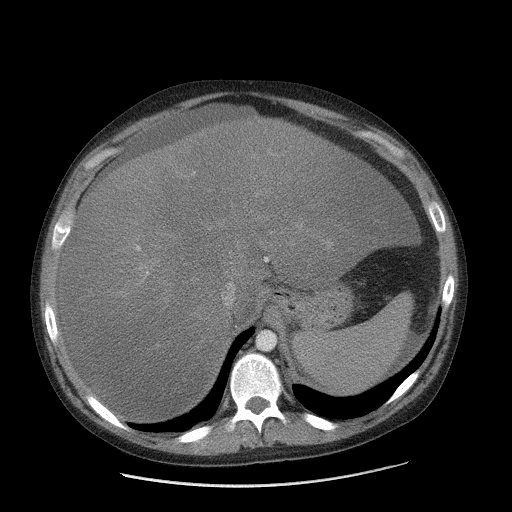

Jak wiadomo NAFLD obejmuje kilka postaci choroby – od prostego stłuszczenia narządu, poprzez zapalenie wątroby w przebiegu schorzenia (NASH – nonalcoholic steatohepatitis), aż po marskość. Wciąż istnieje szereg kontrowersji odnośnie do postępowania farmakologicznego u chorych z NASH. Podstawowym zjawiskiem patofizjologicznym w przebiegu NASH jest obecność procesu zapalnego powstałego w zmienionym histologicznie i „metabolicznie” (stłuszczenie) miąższu wątroby. Kluczową cytokiną jest w tym przypadku czynnik martwicy nowotworów alfa (TNF-α). Jednym z silnych inhibitorów TNF-alfa jest natomiast pentoksyfilina. Stąd istniały podstawy teoretyczne do podjęcia próby oceny skuteczności tego leku w leczeniu chorych z NASH.